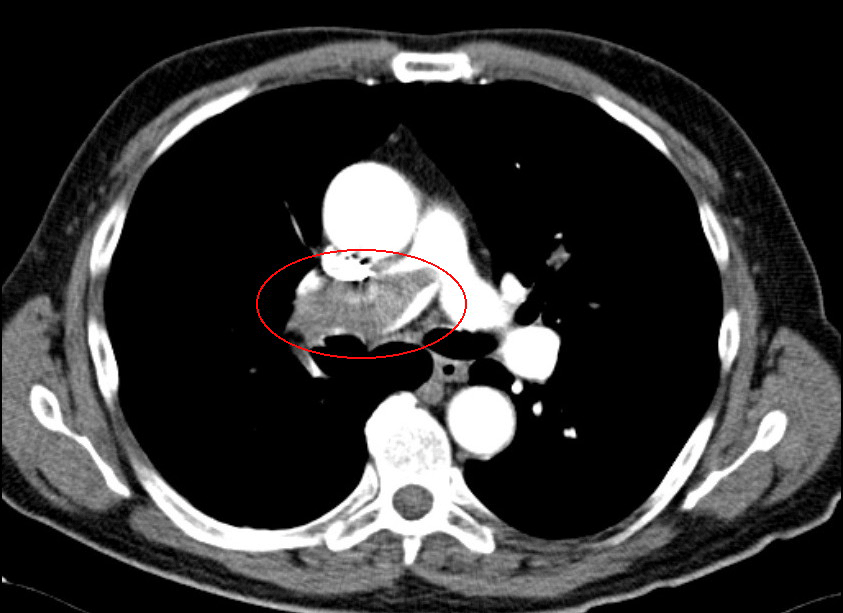

Lungenembolie in der linken Lunge. Lungenembolie in der linken Lunge. © wikipedia/James Heilman, MD (CC BY-SA 4.0)